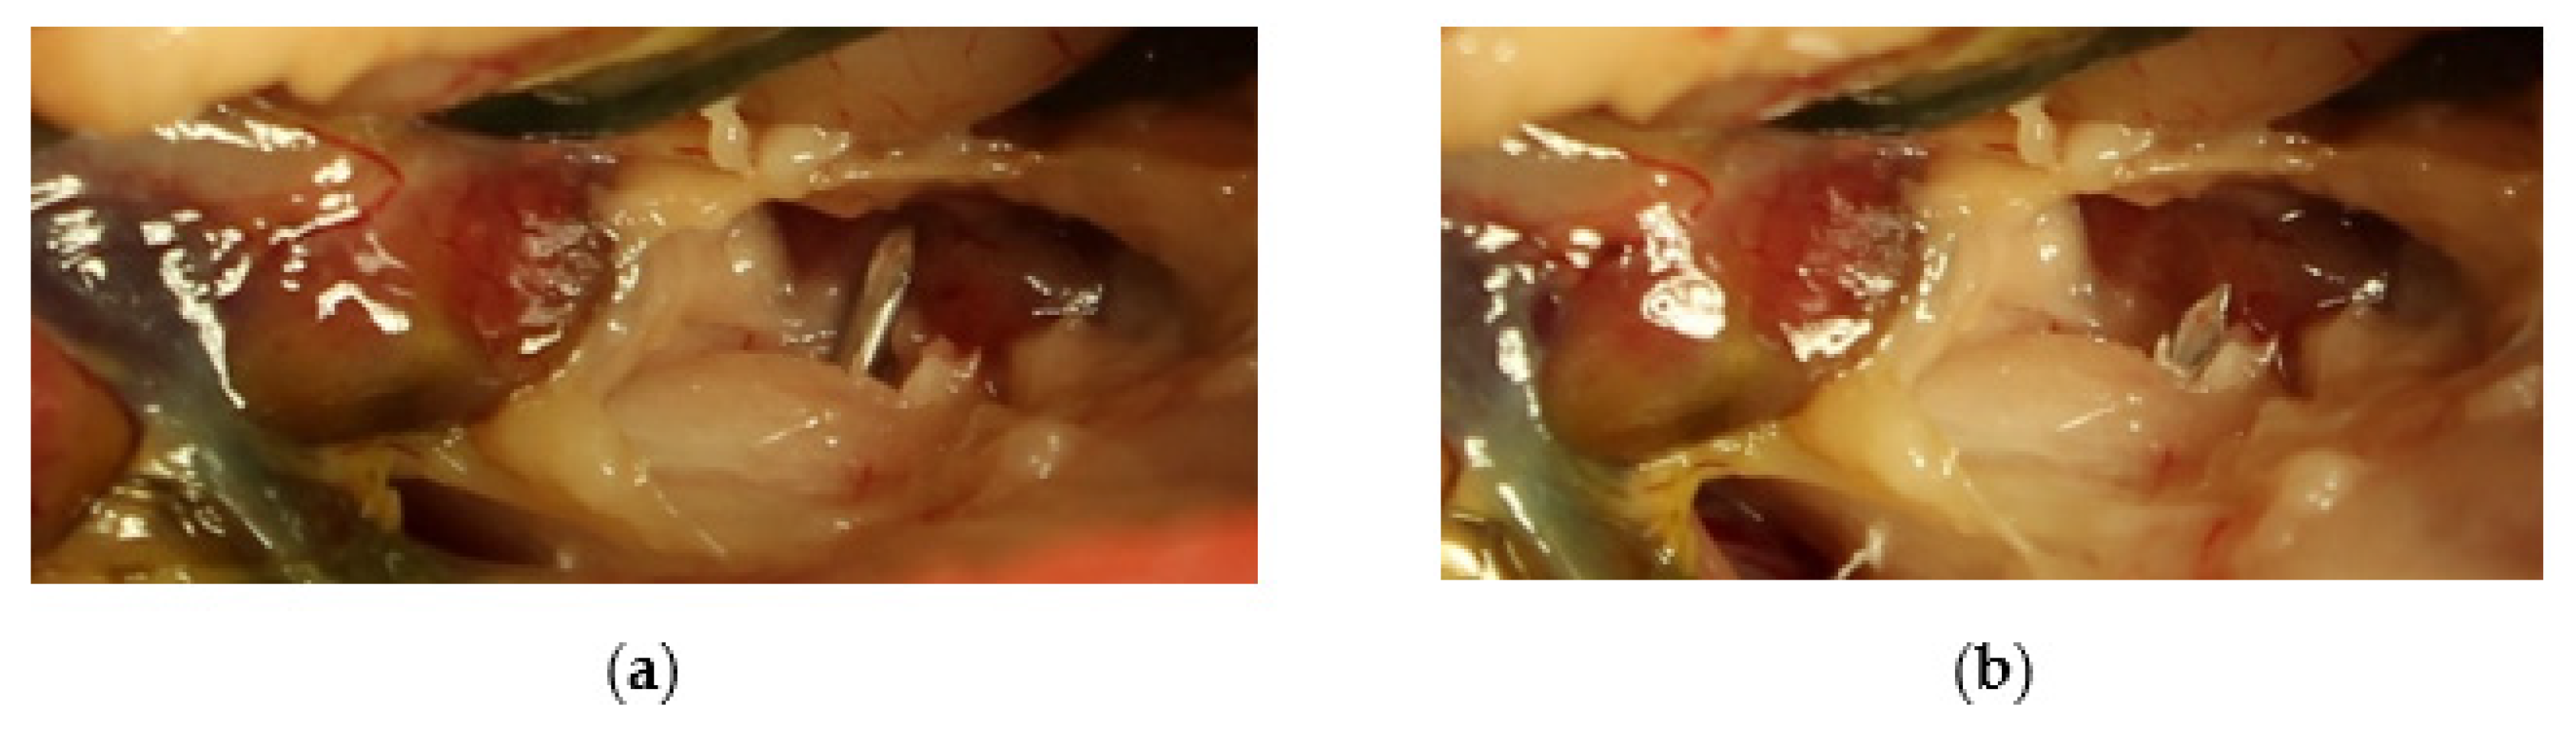

2.2. Surgical Procedure and Post-Surgery Management